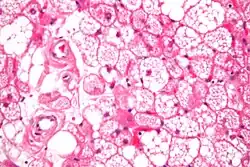

Hibernome sind angeborene Geschwulste des braunen Fettgewebes der Unterhaut, z. B. an Gesäß, Rücken oder Hals, wobei Ähnlichkeit mit der Hibernationsdrüse der Winterschläfer besteht. Sie bestehen aus großen vakuolären, Glykogen- und Phospholipid-reichen Zellen. Braunes Fett ist gelegentlich beim kleinen Säugling flächenhaft im Rücken, um die Nieren und um die Aorta zu finden. Beim Hibernom handelt es sich um seltene, gutartige Tumoren mit Wachstumstendenz. Häufig ist das Hibernom asymptomatisch.